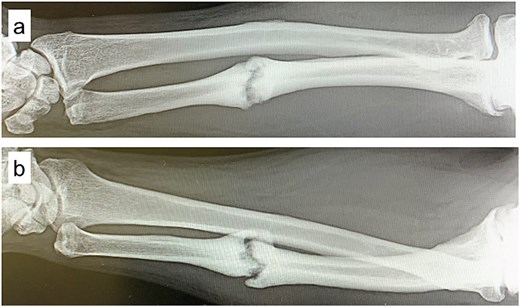

A 54-year-old man sustained a mid-diaphyseal ulnar fracture from a direct kick during karate practice. Initial conservative treatment at another hospital failed to achieve union over 12 months, and he was referred to our clinic with a diagnosis of nonunion. At presentation, he reported significant pain with a numerical rating scale (NRS) score of 6, and radiographs showed a 9 mm interfragmentary gap (Fig. 1a and b). Given his pain, we initiated proactive conservative management with prolotherapy, primarily targeting pain relief. Ultrasound revealed marked doppler signals at the nonunion site, suggesting inflammation and neovascularization. A mixture of 6 ml 50% dextrose and 4 ml 1% lidocaine (final 30% dextrose) was injected under ultrasound guidance into the neovascularized tissue and fracture gap (Fig. 2a and b). From the second session onward, bone healing had progressed to the point where the solution could no longer be injected between the bone fragments, so subsequent injections were administered around the periosteum. No restrictions were placed on weight-bearing or activity. Pain improved to NRS 4 at 2 weeks and to NRS 2 at 4 weeks, with early callus formation seen on radiographs. Prolotherapy was repeated five times at 2–3 week intervals. By 12 weeks, the patient was pain-free (NRS 0) and returned to karate. Radiographic union was confirmed at 15 weeks (Fig. 3a–d). Although initiated for pain control, prolotherapy led to relatively early bone union without surgery or complications.

Plain radiographs at initial presentation. (a, b) Nonunion at the mid-diaphysis of the ulna is observed.

Ultrasound findings and images during the procedure. (a) Ultrasound image at the start of treatment showing marked Doppler signals around the nonunion site. (b) Dextrose injection into the nonunion site under ultrasound guidance.